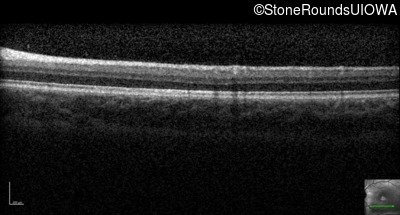

Optical Coherence Tomography - Left - 20/30 sc

Exemplar / OCT Stack